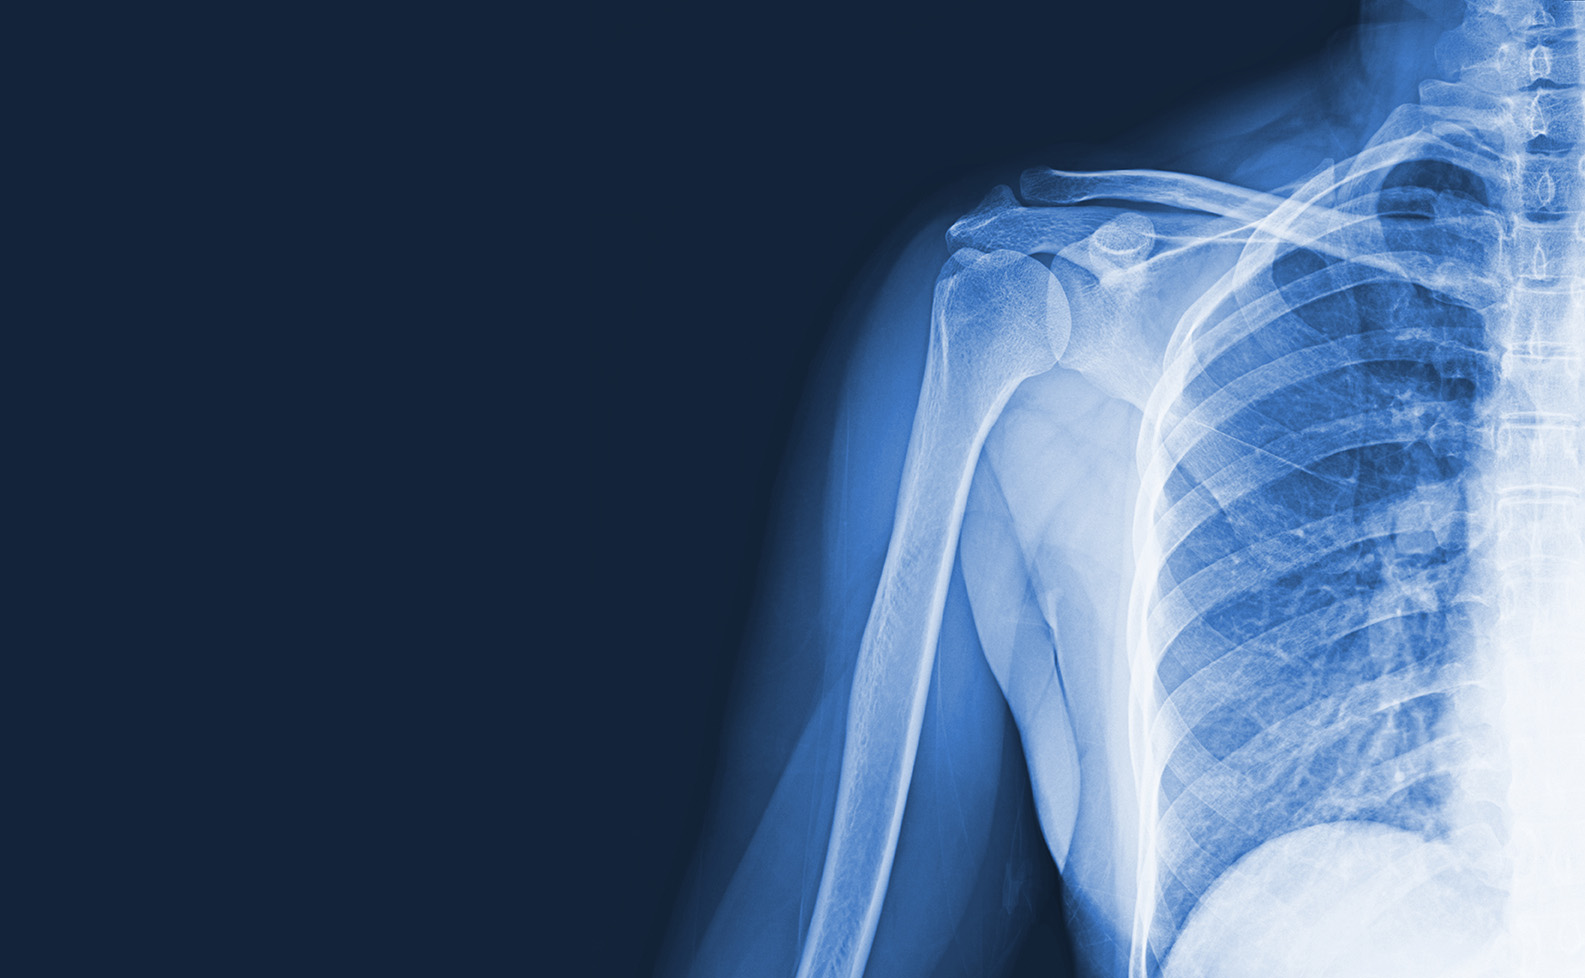

Understanding Your Shoulder Anatomy

Among all your joints, the shoulder is the one you use on the most. As a ball-and-socket joint, it’s the most flexible in the body, allowing for a wide range of motion in many directions.

The “ball” is the head of the humerus, and the “socket” is the glenoid part of the scapula (shoulder blade). Sitting above this joint is the acromion, a common site for bone spurs, while the acromioclavicular (AC) joint nearby is often involved in shoulder separations.

Surrounding these bones is a complex network of muscles, tendons, and ligaments that work together to stabilize and move the shoulder. The rotator cuff—a group of four muscles and their tendons—keeps the shoulder stable while allowing you to lift, rotate, and reach with your arm. The labrum, a ring of cartilage around the socket, helps deepen it and keep the ball of the joint in place.